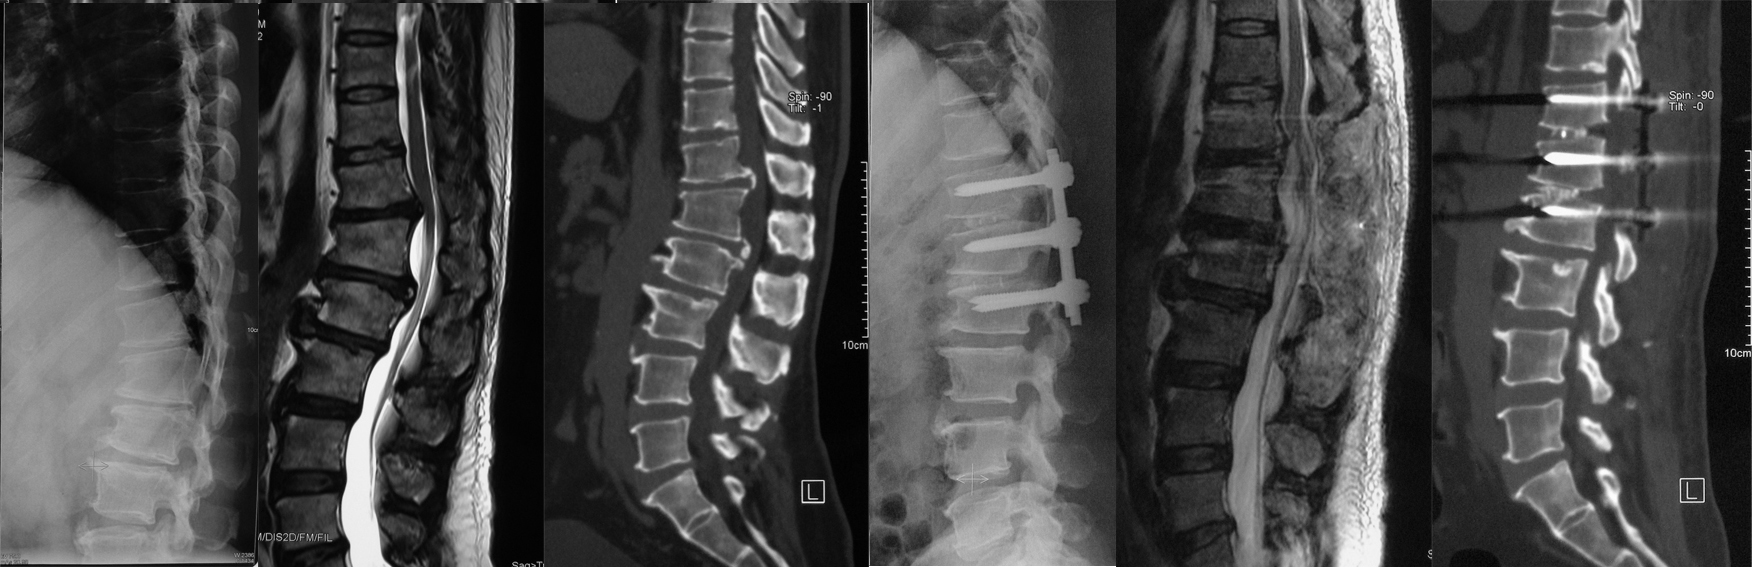

男性,53岁,胸椎管狭窄症(T12-L2椎间盘突出伴骨化),行后路T12-L2经关节突椎间隙外侧缘入路脊髓腹侧减压、固定、融合术。

女性,14岁, L5重度发育不良性滑脱(ⅴ°),行前后联合入路L5椎切除、S1上终板截骨、L4-S1固定融合术。

女性 67岁,腰椎管狭窄症,L4退变性I度滑脱,后路微创通道下减压复位、经皮椎弓根螺钉内固定术